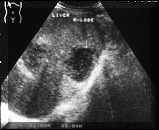

Abscesses of some duration :

The basic difference between an acute abscess and an abscess of some duration is that, in the latter the body has had time to wall up the lesion by producing a layer of fibrous tissue around it. On sonography an abscess shows thick walls which may vary from a few mm to 1.5 cm in thickness. The echogenicity of the abscess also varies, abscesses generally become more sonolucent at this stage, some abscesses become more echogenic because of organisation of fluid (see Picture3).

Picture3.